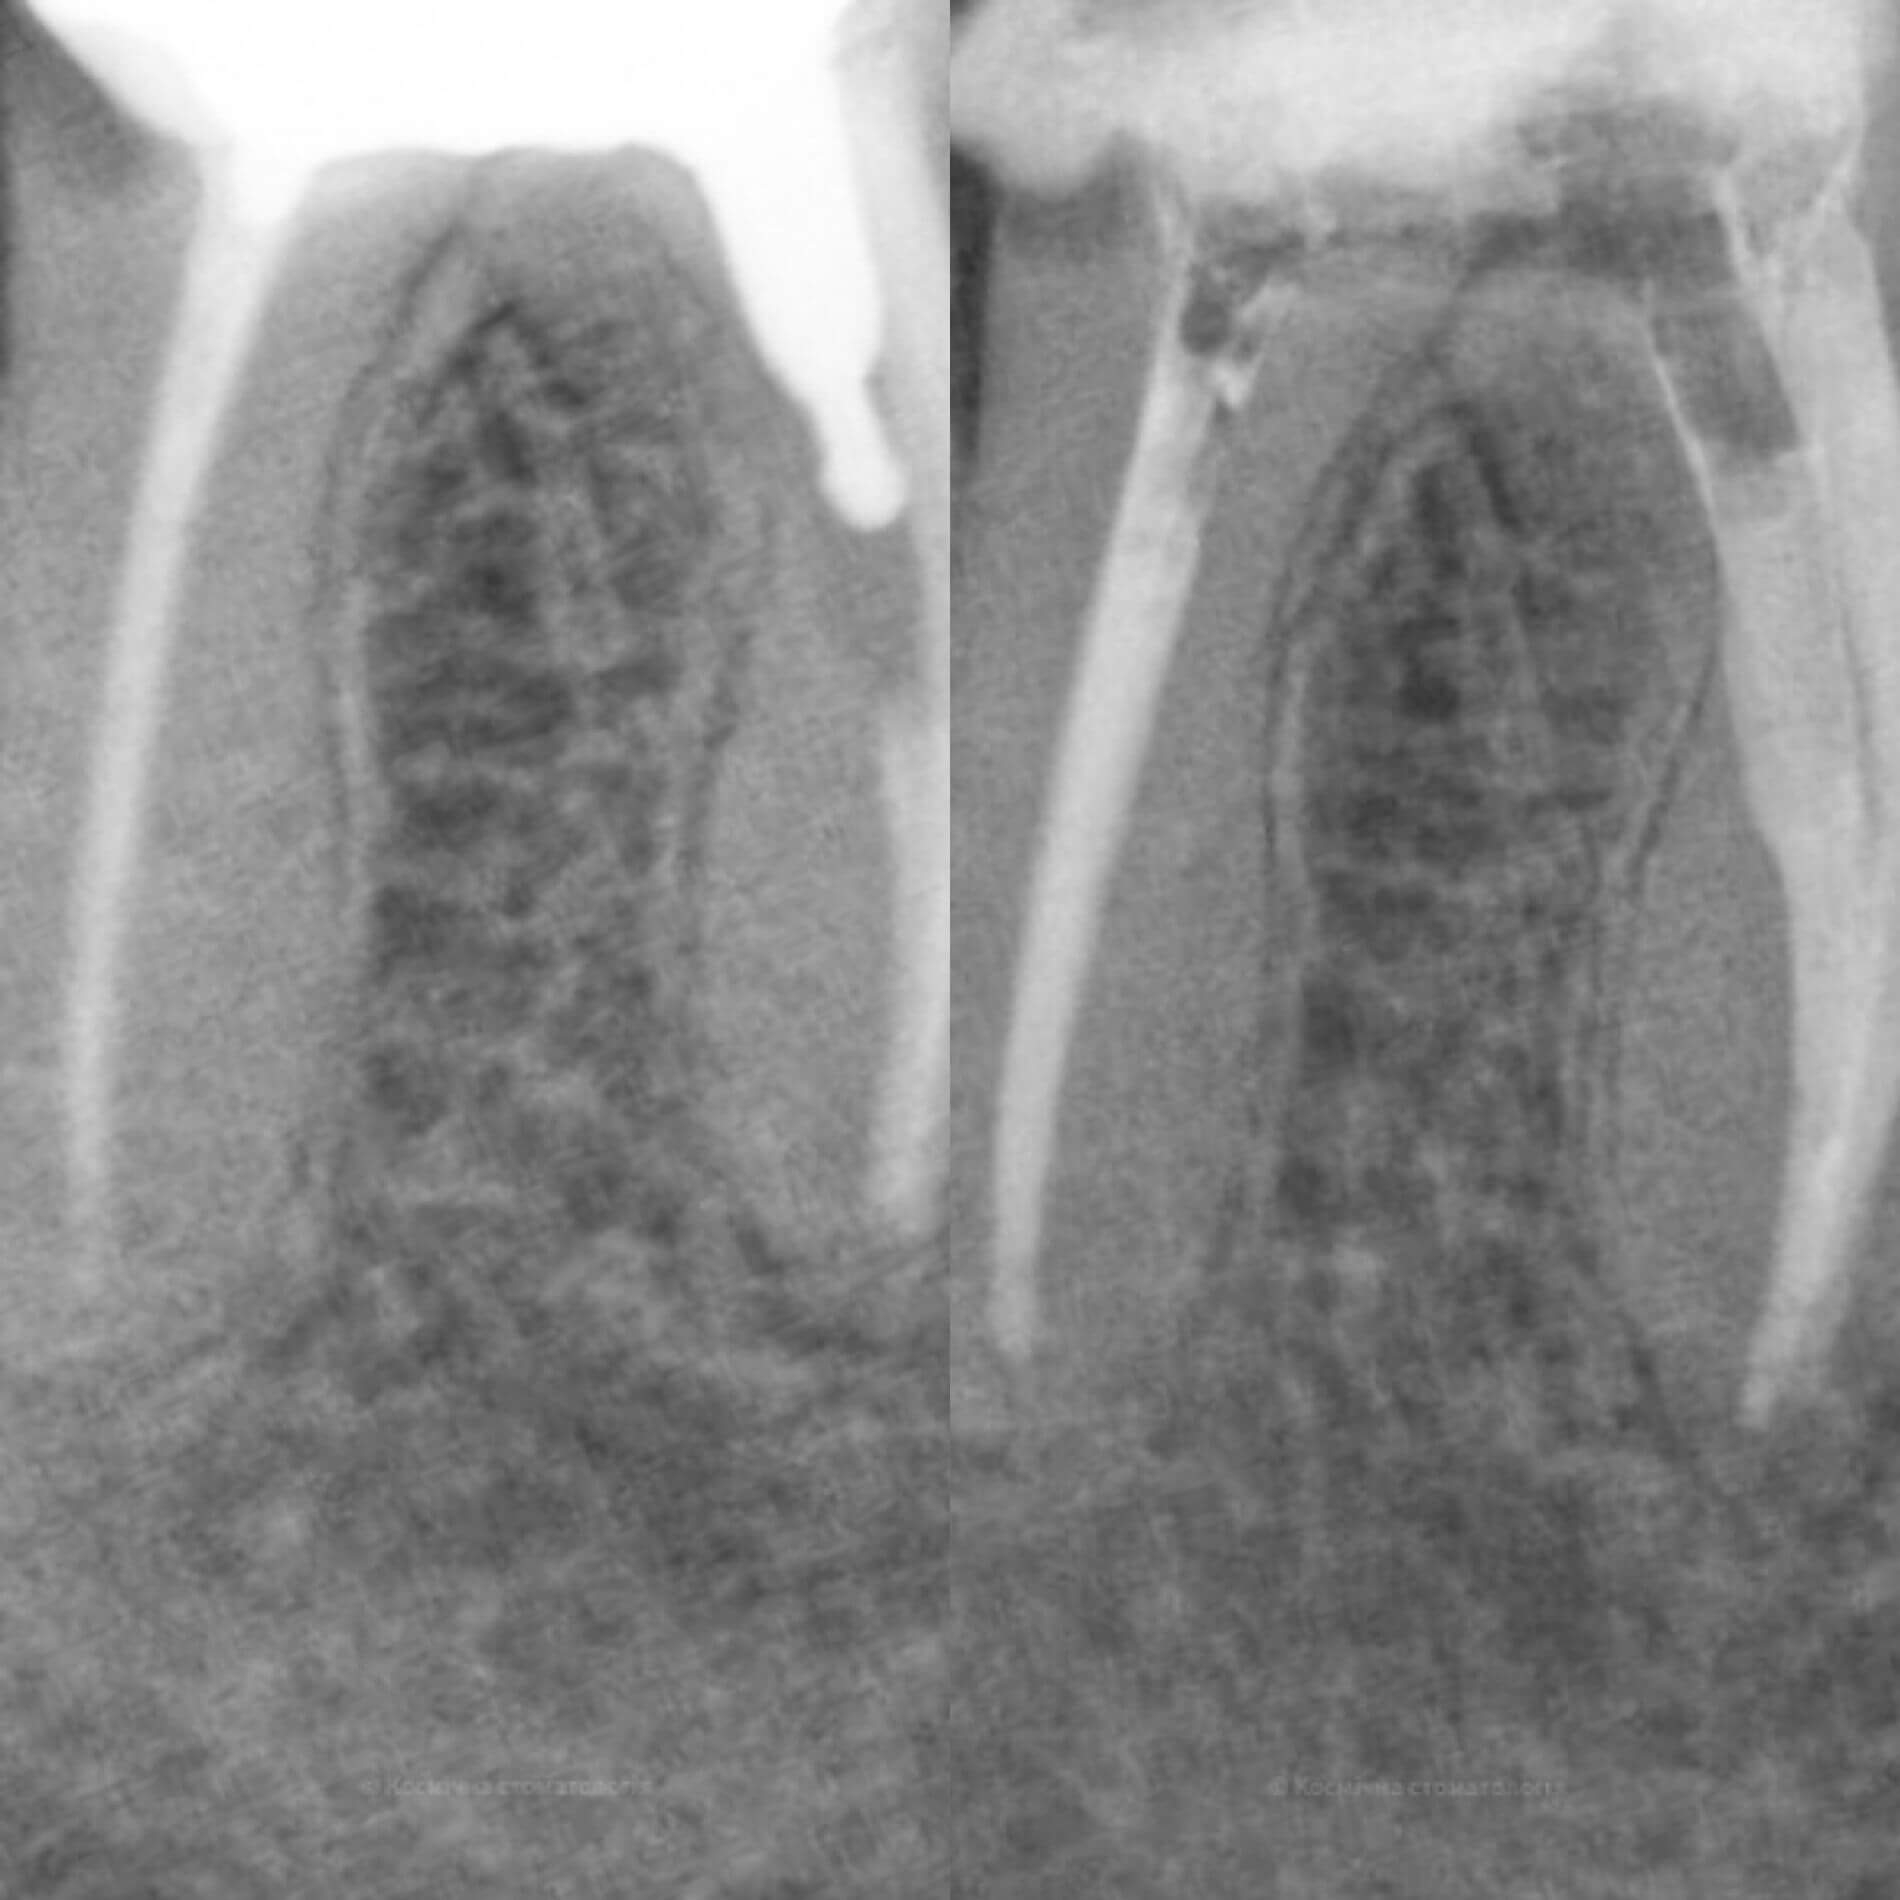

Мы уже говорили, качественное лечение зубных каналов – это довольно сложный и трудоемкий процесс, но с ним с легкостью справится наша космическая команда. Эта процедура затруднена отсутствием полноценного доступа к операционной полости, да еще зубные каналы часто искривлены и очень узкие, что делает невозможным визуальный контроль за проведением процедуры.

Но инновационные технологии и применение рентгенологического контроля выводят лечение каналов зуба во Львове специалистами Космической стоматологии Драганчука на новый межгалактический уровень.

- 3D пломбирование корневых каналов горячей гуттаперчей. Высокоэффективная техника, позволяющая заполнить все ответвления корневых каналов настолько плотно, чтобы достичь абсолютной герметизации. А значит, ни одна инфекция не сможет повторно поразить корневые каналы твоего зуба.

Чтобы провести процедуру лечения и пломбирования каналов, мы в космической стоматологии Драганчука используем оптическое увеличение с помощью микроскопа Carl Zeisse.

Он позволяет вывести изображение на большой экран и масштабировать его, чтобы наша космическая команда могла осуществить все необходимые манипуляции особенно скрупулезно. Благодаря такому оптическому контролю каждого этапа лечения, мы можем оценить его эффективность и предотвратить возникновение осложнений.